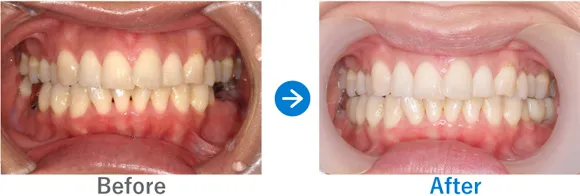

ブリッジで両隣の歯もダメに…。インプラント治療後は奥歯でしっかり噛めるように!

右下7はかなり前に抜歯後、ブリッジ治療済み。左下6は抜歯後、義歯を入れたがほとんど使っていない

インプラント4本:右下6・7、左下6・7

1,249,500円(内訳:GBR、インプラント4本(ネオデント)、ガイド、仮歯、セデーション、骨補填材、保証20年)

治療結果

来院時の検査で、骨はやせてはいたものの治っている状態だったので、インプラント埋入と同時に骨補填をし、下顎の左右に2本ずつインプラントを埋入し治療完了しました。しっかり噛めるようになり患者様も喜んでおられます。今後はナイトガードを使用して、ブラキシズム(無意識下の歯ぎしり、食いしばりなど)の予防をしていく予定です。